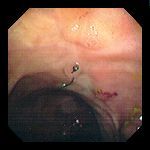

Внешний вид швов, сохранившихся после операции на ободочной кишке. Часто имеется сопутствующая воспалительная реакция (обратите внимание на очаговый эксудат на фото#1). Иногда реакция имеет полиповидную форму (фото#3), имитируя неоплазию.